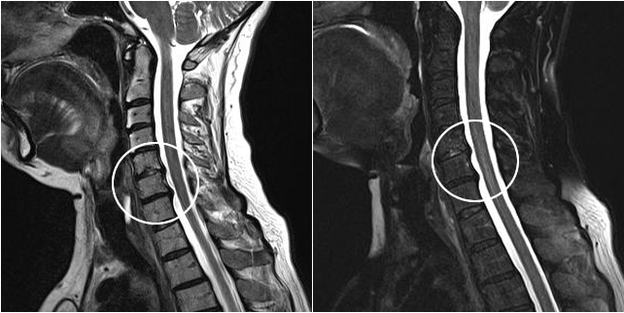

Modern diagnostic methods include MRI and CT, which make it possible to examine the processes of destruction of cartilage and bone tissue in the most accurate way.Also, using this technique, it is convenient to diagnose hernias and other soft tissue defects near the source of the disease.